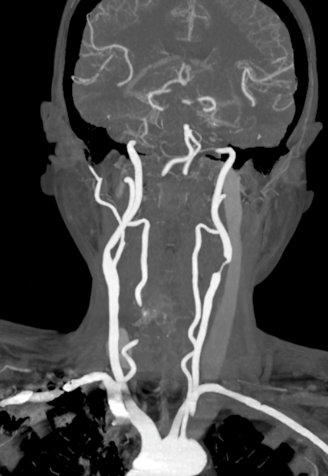

头颈部CTA

波科支架怎么样径技-弓上病例大赏|第205期·放疗后症状性颈动脉狭窄支架置入治疗一例_https://www.jmylbn.com_新闻资讯_第9张

波科支架怎么样径技-弓上病例大赏|第205期·放疗后症状性颈动脉狭窄支架置入治疗一例_https://www.jmylbn.com_新闻资讯_第10张

波科支架怎么样径技-弓上病例大赏|第205期·放疗后症状性颈动脉狭窄支架置入治疗一例_https://www.jmylbn.com_新闻资讯_第11张